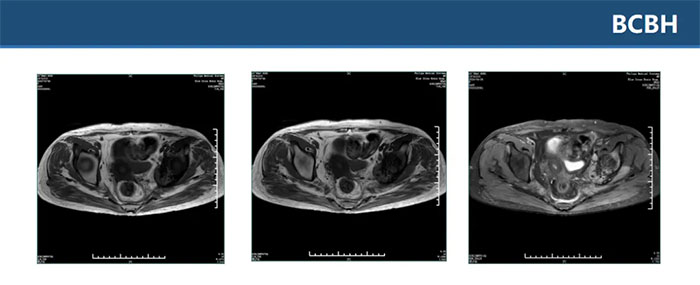

▲ 双侧骶丛神经平扫+增强未见明显异常,L2、L4、骶S1-3椎体及其附件区多发异常信号影

▲ 双侧坐骨、髂骨、骶骨、左侧耻骨多发异常信号伴左髂骨髋臼处骨质破坏,考虑肿瘤性病变,转移瘤待排